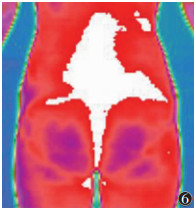

服用温经汤1个疗程后,子宫及宫颈区细胞代谢热明显较前增加,热断层过程中与腹股沟淋巴迅速连成一片;下腹部及腰骶部向上的脊柱可见竖条状细胞代谢热增加,呈上升趋势,热辐射值均明显高于用药前(均P < 0.05)(图 4~6)。

![]() |

| 图 6 女,23岁,原发性寒湿凝滞型痛经,下腹部及腰骶部向上的脊柱可见竖条状细胞代谢热增加,呈上升趋势 |